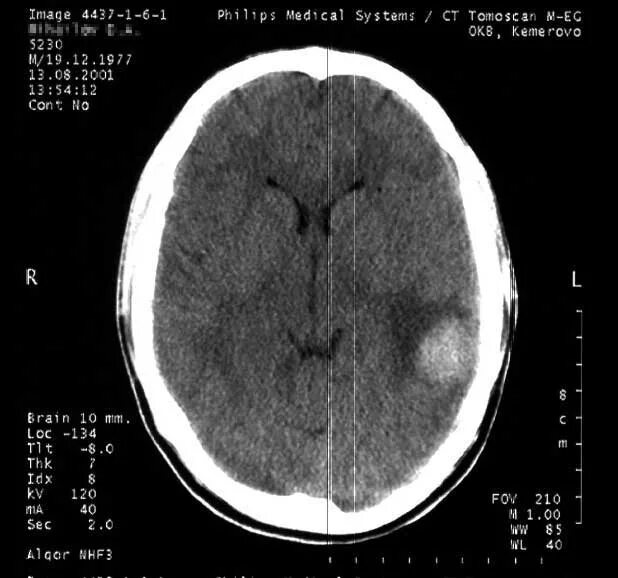

Ушиб мозга на кт